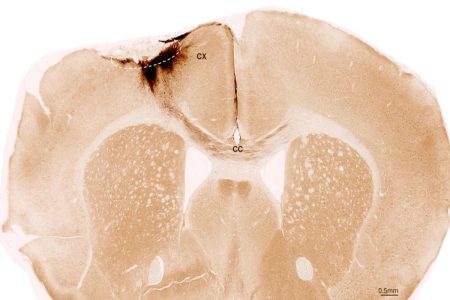

Η αμερικανική ερευνητική ομάδα πέτυχε να αφαιρέσει το μισό γενετικό υλικό από τα 82 ωάρια που δημιούργησε στο εργαστήριο με το παραπάνω πρωτόκολλο. Ωστόσο μόνο το 10% αυτών έδωσε, μετά τη γονιμοποίησή τους, βιώσιμα έμβρυα 6 ημερών. Βεβαίως κανένα δεν εμφυτεύθηκε!